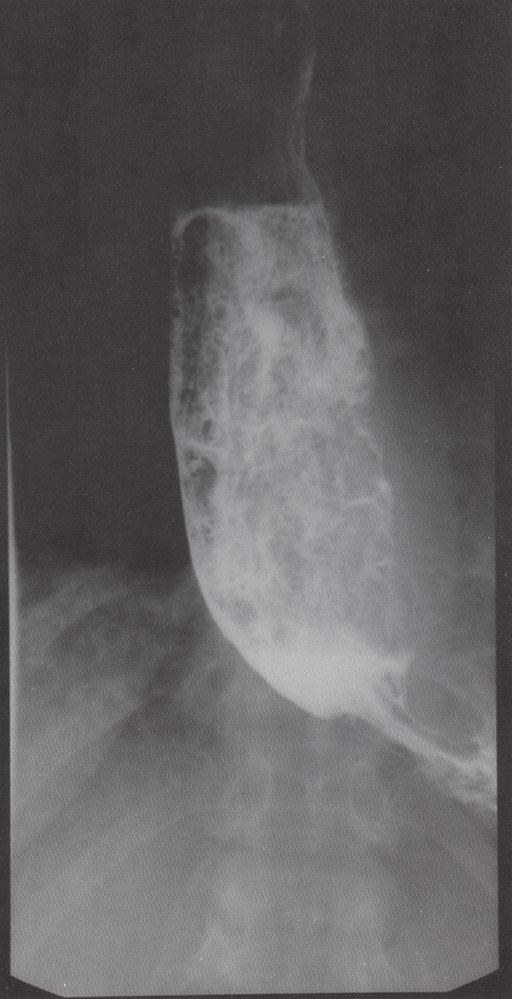

• Bird-beak sign: dilatation of the proximalesophagus with stenosis of the gastroesophageal junction

• Dilated esophagus that tapers distally (bird-beak sign/rat's tail appearance)